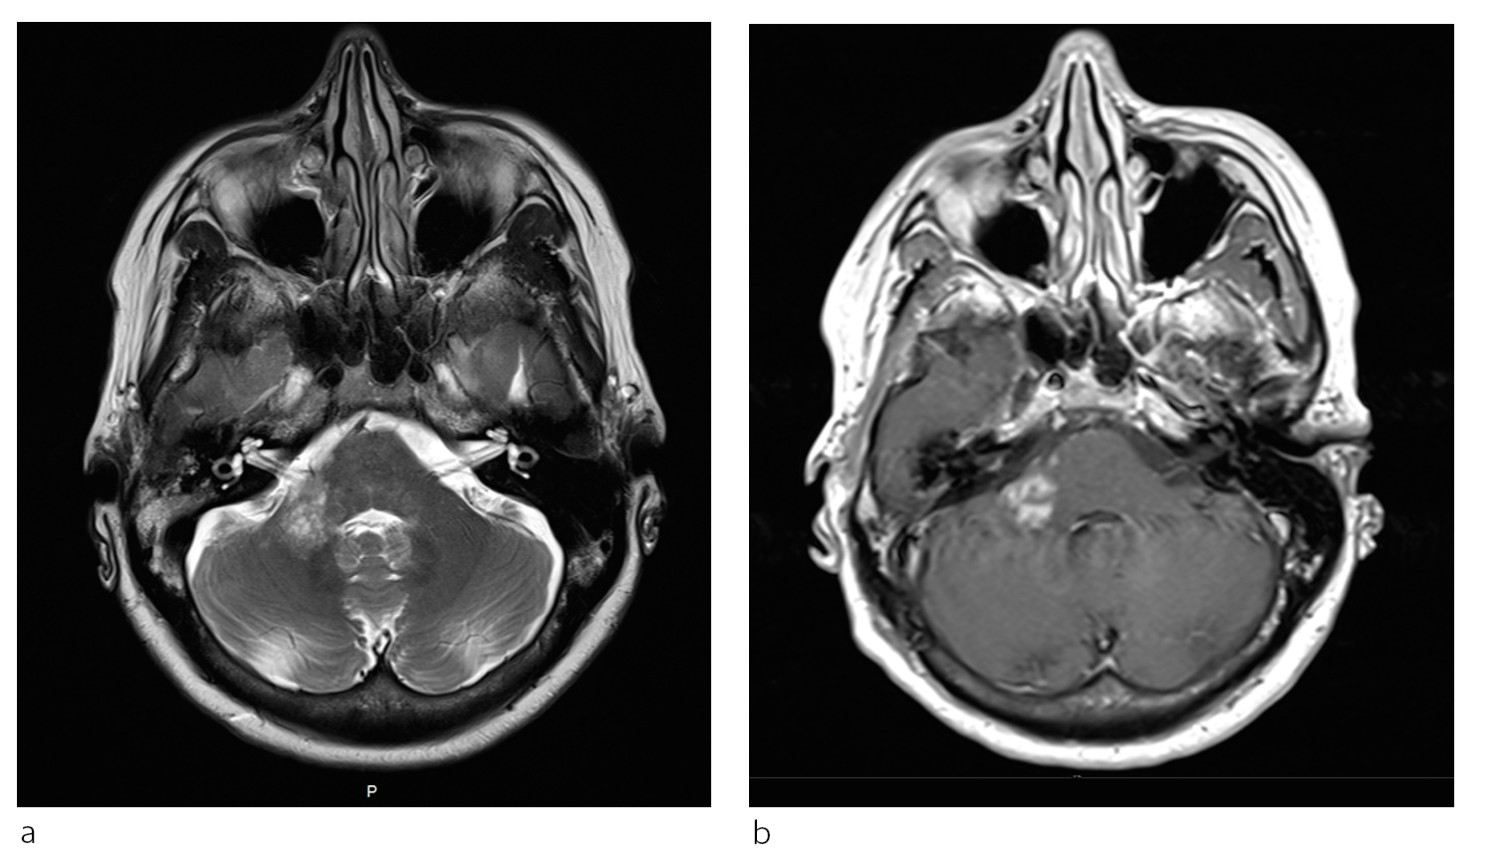

Pasient 2. En kvinne i 50-årene med attakkpreget multippel sklerose var blitt behandlet med natalizumab (Tysabri) over flere år da hun fikk påvist diskrete forandringer på en MR-undersøkelse. Hun hadde da ikke hatt tegn til sykdomsaktivitet på flere år. JCV-antistoff var blitt påvist i serum to år tidligere, men indeks var ikke tilgjengelig på dette tidspunktet. Natalizumab ble seponert, men pasienten utviklet etter hvert likevel ustøhet og dobbeltsyn, og MR-undersøkelse to måneder senere viste betydelig økning av forandringer (fig 2a). Det var en inhomogen høyattenuerende forandring i høyre lillehjernestilk som ikke er lett å skille fra en forandringer ved multippel sklerose. PCR-undersøkelse av JCV-DNA avdekket 1 173 kopier/ml i spinalvæske.

Plasmaferesebehandling ble gitt, men symptomene progredierte. Ny MR-undersøkelse tre uker senere viste kontrastladende lesjoner, forenlig med immunrekonstitusjonsinflammasjonssyndrom (fig 2b). Pasienten fikk høydose metylprednisolon (Solu-medrol), med påfølgende remisjon. Hun ble frisk fra progredierende multifokal leukoencefalopati, men fikk sekvele.